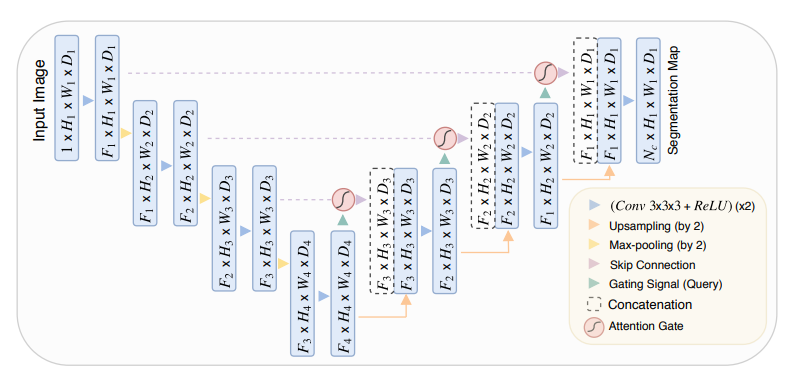

Attention U-Net 是一种改进的 U-Net 分割网络,通过引入注意力机制(Attention Mechanism),增强了网络对目标区域的聚焦能力,尤其在医学图像分割任务中表现出色。它在保留 U-Net 对称编码器-解码器结构的基础上,结合了注意力门(Attention Gate, AG),使网络能够自动突出感兴趣区域的特征,同时抑制不相关的背景信息。

Attention U-Net 的整体架构由编码器、解码器和注意力模块组成:

编码器部分负责提取输入图像的多尺度特征。输入图像经过一系列卷积操作、激活函数(通常是ReLU)、批归一化(Batch Normalization)以及最大池化操作,逐步降低分辨率并提取深层特征。

解码器部分逐步恢复特征图的空间分辨率。通过上采样操作(如反卷积或双线性插值),解码器结合编码器的高分辨率特征图恢复目标区域的细节。跳跃连接(Skip Connection)在解码过程中将编码器的特征图直接传递给对应的解码层,确保局部细节信息不丢失。

注意力机制是 Attention U-Net 的核心改进。网络在跳跃连接中引入了注意力门模块,用于选择性地突出相关特征并过滤掉无关区域。注意力门通过计算特征图中的权重分布,使网络更加聚焦于感兴趣区域(如病灶或解剖结构)。具体来说,注意力门会对编码器的特征图和解码器的特征图进行加权融合,生成注意力掩膜(Attention Mask),从而动态调整特征图的权重。这样可以有效提高网络对目标边界的敏感性,同时减少背景噪声的干扰。

最终输出层通过 1x1 的卷积操作生成分割结果,通道数与分割类别数相同。激活函数(如Sigmoid或Softmax)将网络输出映射为像素级概率,用于生成分割掩膜。

Attention U-Net 的优点在于其通过注意力机制显著提高了分割的准确性和鲁棒性,特别是在目标区域较小或边界复杂的情况下。它不仅能增强对感兴趣区域的响应,还能有效降低背景区域的干扰,适用于各种高精度要求的医学图像分割任务。